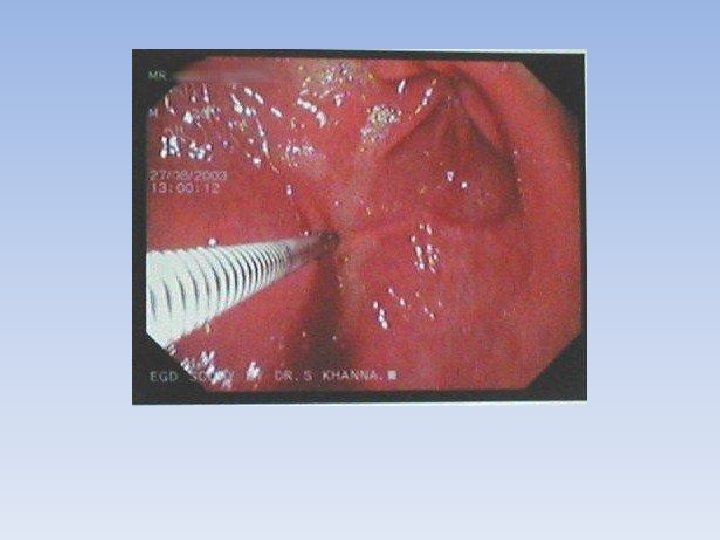

Biophotonics • Light is shone on cells and tissues. The light is scattered by the molecules of the cells and a special device is used to record these scatter patterns. • This produces an image. • Doctors can things like endoscopes to examine deep inside the body. An endoscope is a thin tube with a bright light and a camera.